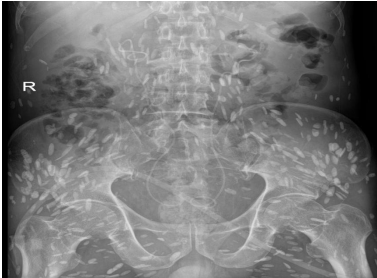

The patient, male, 69 years old, BMI: 20.03 kg/m, was admitted to the hospital for more than three months due to low back pain and discomfort. Before admission, magnetic resonance urography (MRU) showed that both kidneys and the middle and upper ureters were dilated with hydrops, and retroperitoneal fibrosis was possible. Renal function test showed: creatinine: 356 umol/L, urea: 20.97 mmol/L. After admission, plain and enhanced abdominal and pelvic scans showed: [1] abnormal density around the abdominal aorta and bilateral ureters, considering the possibility of idiopathic retroperitoneal fibrosis (Figure 1A), please combine clinical; [2] change of chronic pancreatitis; [3] abnormal enhancement of pancreas and left kidney parenchyma, consider abnormal perfusion, follow-up; [4] local abnormal density in venous phase of left internal lobe of liver, consider local poor perfusion; [5] right kidney atrophy; bilateral renal pelvis and bilateral The upper segment of the ureter was dilated with hydrops; [6] pleural effusions and ascites were present on both sides; [7] there were multiple short-strip high-density shadows in the subcutaneous and abdominal pelvic cavity of the chest, abdomen, and pelvis, and calcification of cysticercosis was considered (Figure 1B); [8] prostate calcification; [9] the right renal artery was slender, and calcified plaques formed at the origin of bilateral renal arteries and abdominal aorta. Renal function test showed: creatinine: 376.0 mmol/L, urea: 23.4 mmol/L, K+: 6.0 mmol/L. Ureteroscopy and bilateral ureteral stent placement were performed. Postoperative re-examination of kidney ureter bladder (KUB) showed the presence of bilateral ureteral stents (Figure 2). The patient's creatinine was 331.2 mmol/L, creatinine was 25.1 mmol/L, and K+ was 4.0 mmol/L 3 days after surgery. The patient was followed up after discharge for 2 years, during which the double J tube was replaced every six months. The creatinine was close to 170 mmol/L, urea was close to 12.9 mmol/L, and K+ was normal.

Figure 1: Abdominal and pelvic plain scan + enhancement (A); abnormal density around the abdominal aorta and bilateral ureters may be considered as idiopathic retroperitoneal fibrosis (B); there are multiple short-stripe high-density shadows in the thoracoabdominal subcutaneous and abdominal pelvic cavity, and cysticercosis calcification is considered.

Figure 2: kidney ureter bladder (KUB), after ureteral stent placement.